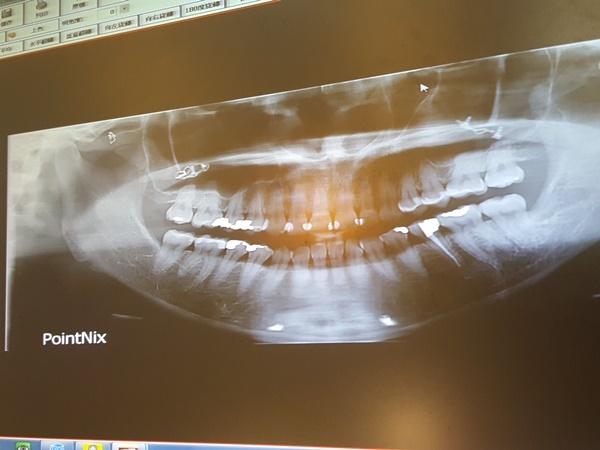

預約做冷光美白前牙醫師建議美白前要先到院內做牙齒檢查

順便清清牙齒上的牙結石

這樣做冷光美白效果才會比較好

蛀牙檢查時牙醫師很仔細每一顆牙都輕磨慢洗

冷光美白前一樣也是需要先確認齒面有沒有蛀牙

補好蛀牙就順便洗牙去除牙結石

再將牙齒進行拋光使茶垢或是色斑清除乾淨

然後牙醫師會確認牙齦敏感情況後才施作

牙齦跟齒質健康沒有甚麼蛀牙

牙醫師才願意替我做冷光美白